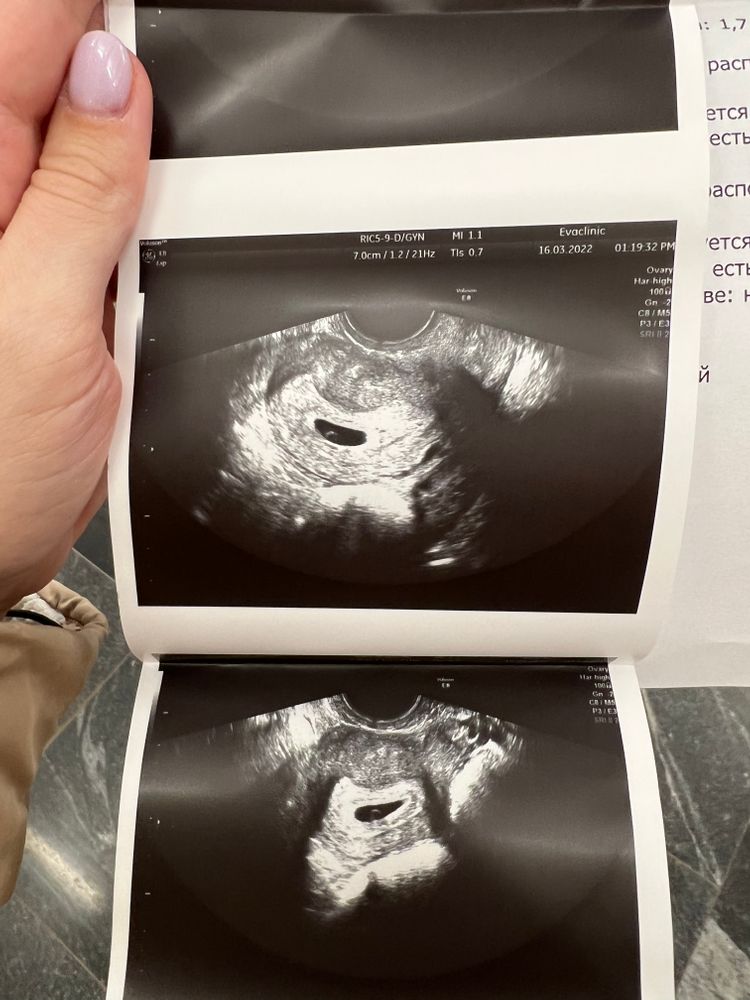

Помогите расшифровать УЗИ🙏🏻

По акушерскому сроку у меня уже полноценная 6 неделя должна быть, но я успокаиваю себя тем, что у меня длинный цикл и возможно была овуляция попозже.

Эмбриона не видно пока.

Jimmy Vatko, сказали срок 5 недель по узи, а акушерский у меня 6.5 уже , вот, переживаю . Просто была ЗБ первая